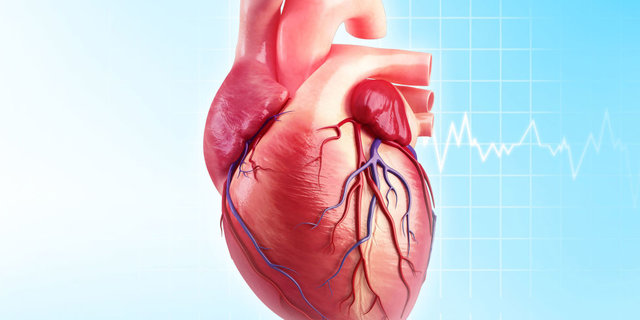

قیمت: 108٬000 تومان - دسته بندی فایل: پاورپوینتپاورپوینت بیماری های دریچه ای قلب

فروش ویژه پاور پوینت حرفه ای بیماری های دریچه ای قلب با تخفیف استثنایی فقط 103 هزار تومان تعداد اسلاید: 67 اسلاید

قیمت: 60٬983 تومان - دسته بندی فایل: پاورپوینتدانلود پاورپوینت فیزیولوژی قلب و دستگاه گردش خون

خرید و دانلود پاورپوینت کامل و آماده ارائه پاورپوینت فیزیولوژی قلب و دستگاه گردش خون